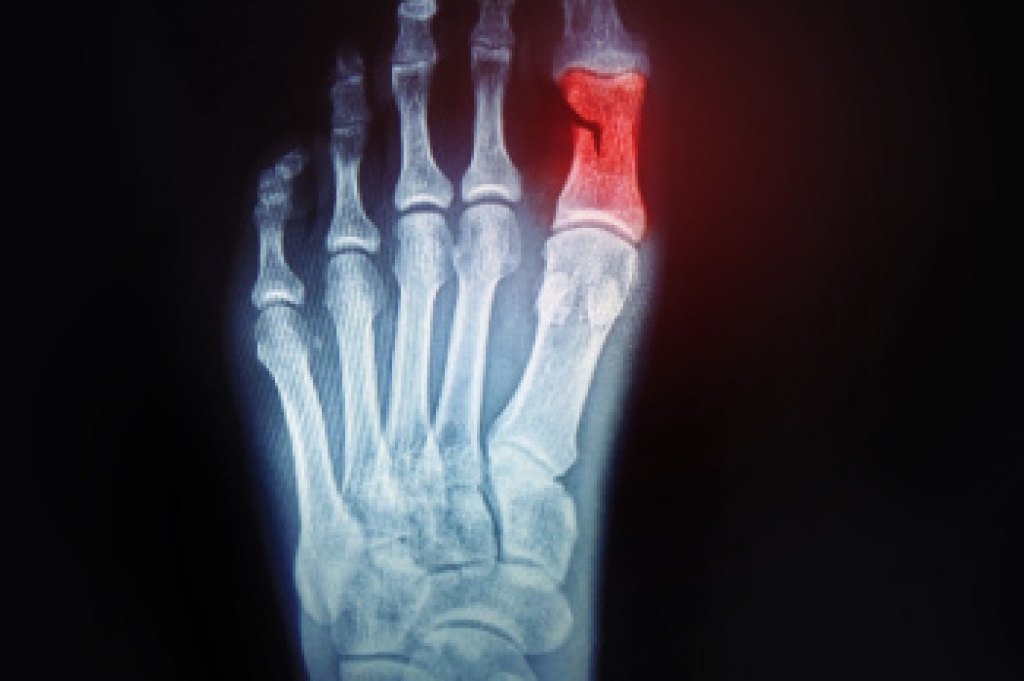

A mid-foot stress fracture is a small crack in one of the bones in the middle of the foot. It often affects the navicular bone, which helps support body weight when walking and running. This fracture develops gradually from repeated impact, such as running, jumping, or sudden increases in activity. Risk factors include training on a hard surface, foot alignment problems, and wearing shoes that lack adequate support. Symptoms include tenderness, swelling, and a deep, aching pain that worsens when bearing weight. Because signs can be subtle, the injury is sometimes missed without proper imaging. A podiatrist can examine the foot, check for areas of pain, and order imaging scans or X-rays to confirm the diagnosis. Treatment options include a cast, custom orthotics, or surgery in more severe cases. If you have symptoms of mid-foot pain, it is suggested that you make an appointment with a podiatrist for diagnosis and treatment.

Stress fractures are the result of repetitive force being placed on the bone. Since the lower leg and feet often carry most of the body’s weight, stress fractures are likely to occur in these areas. If you rush into a new exercise, you are more likely to develop a stress fracture since you are starting too much, too soon. Pain resulting from stress fractures may go unnoticed at first, however it may start to worsen over time.